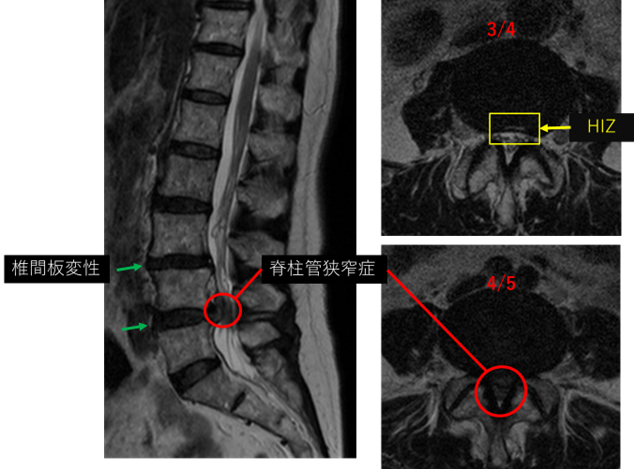

画像及び所見について

L1/2: 異常なし

L2/3: 異常なし

L3/4: 椎間板変性、膨隆、HIZ

L4/5: 椎間板変性、膨隆、両側椎間孔狭窄、脊柱管狭窄症

L5/S: 異常なし

以上の事が画像上認められます。

3/4、4/5に椎間板変性、椎間孔狭窄、脊柱管狭窄症を認め、主症状の原因の可能性が高い。